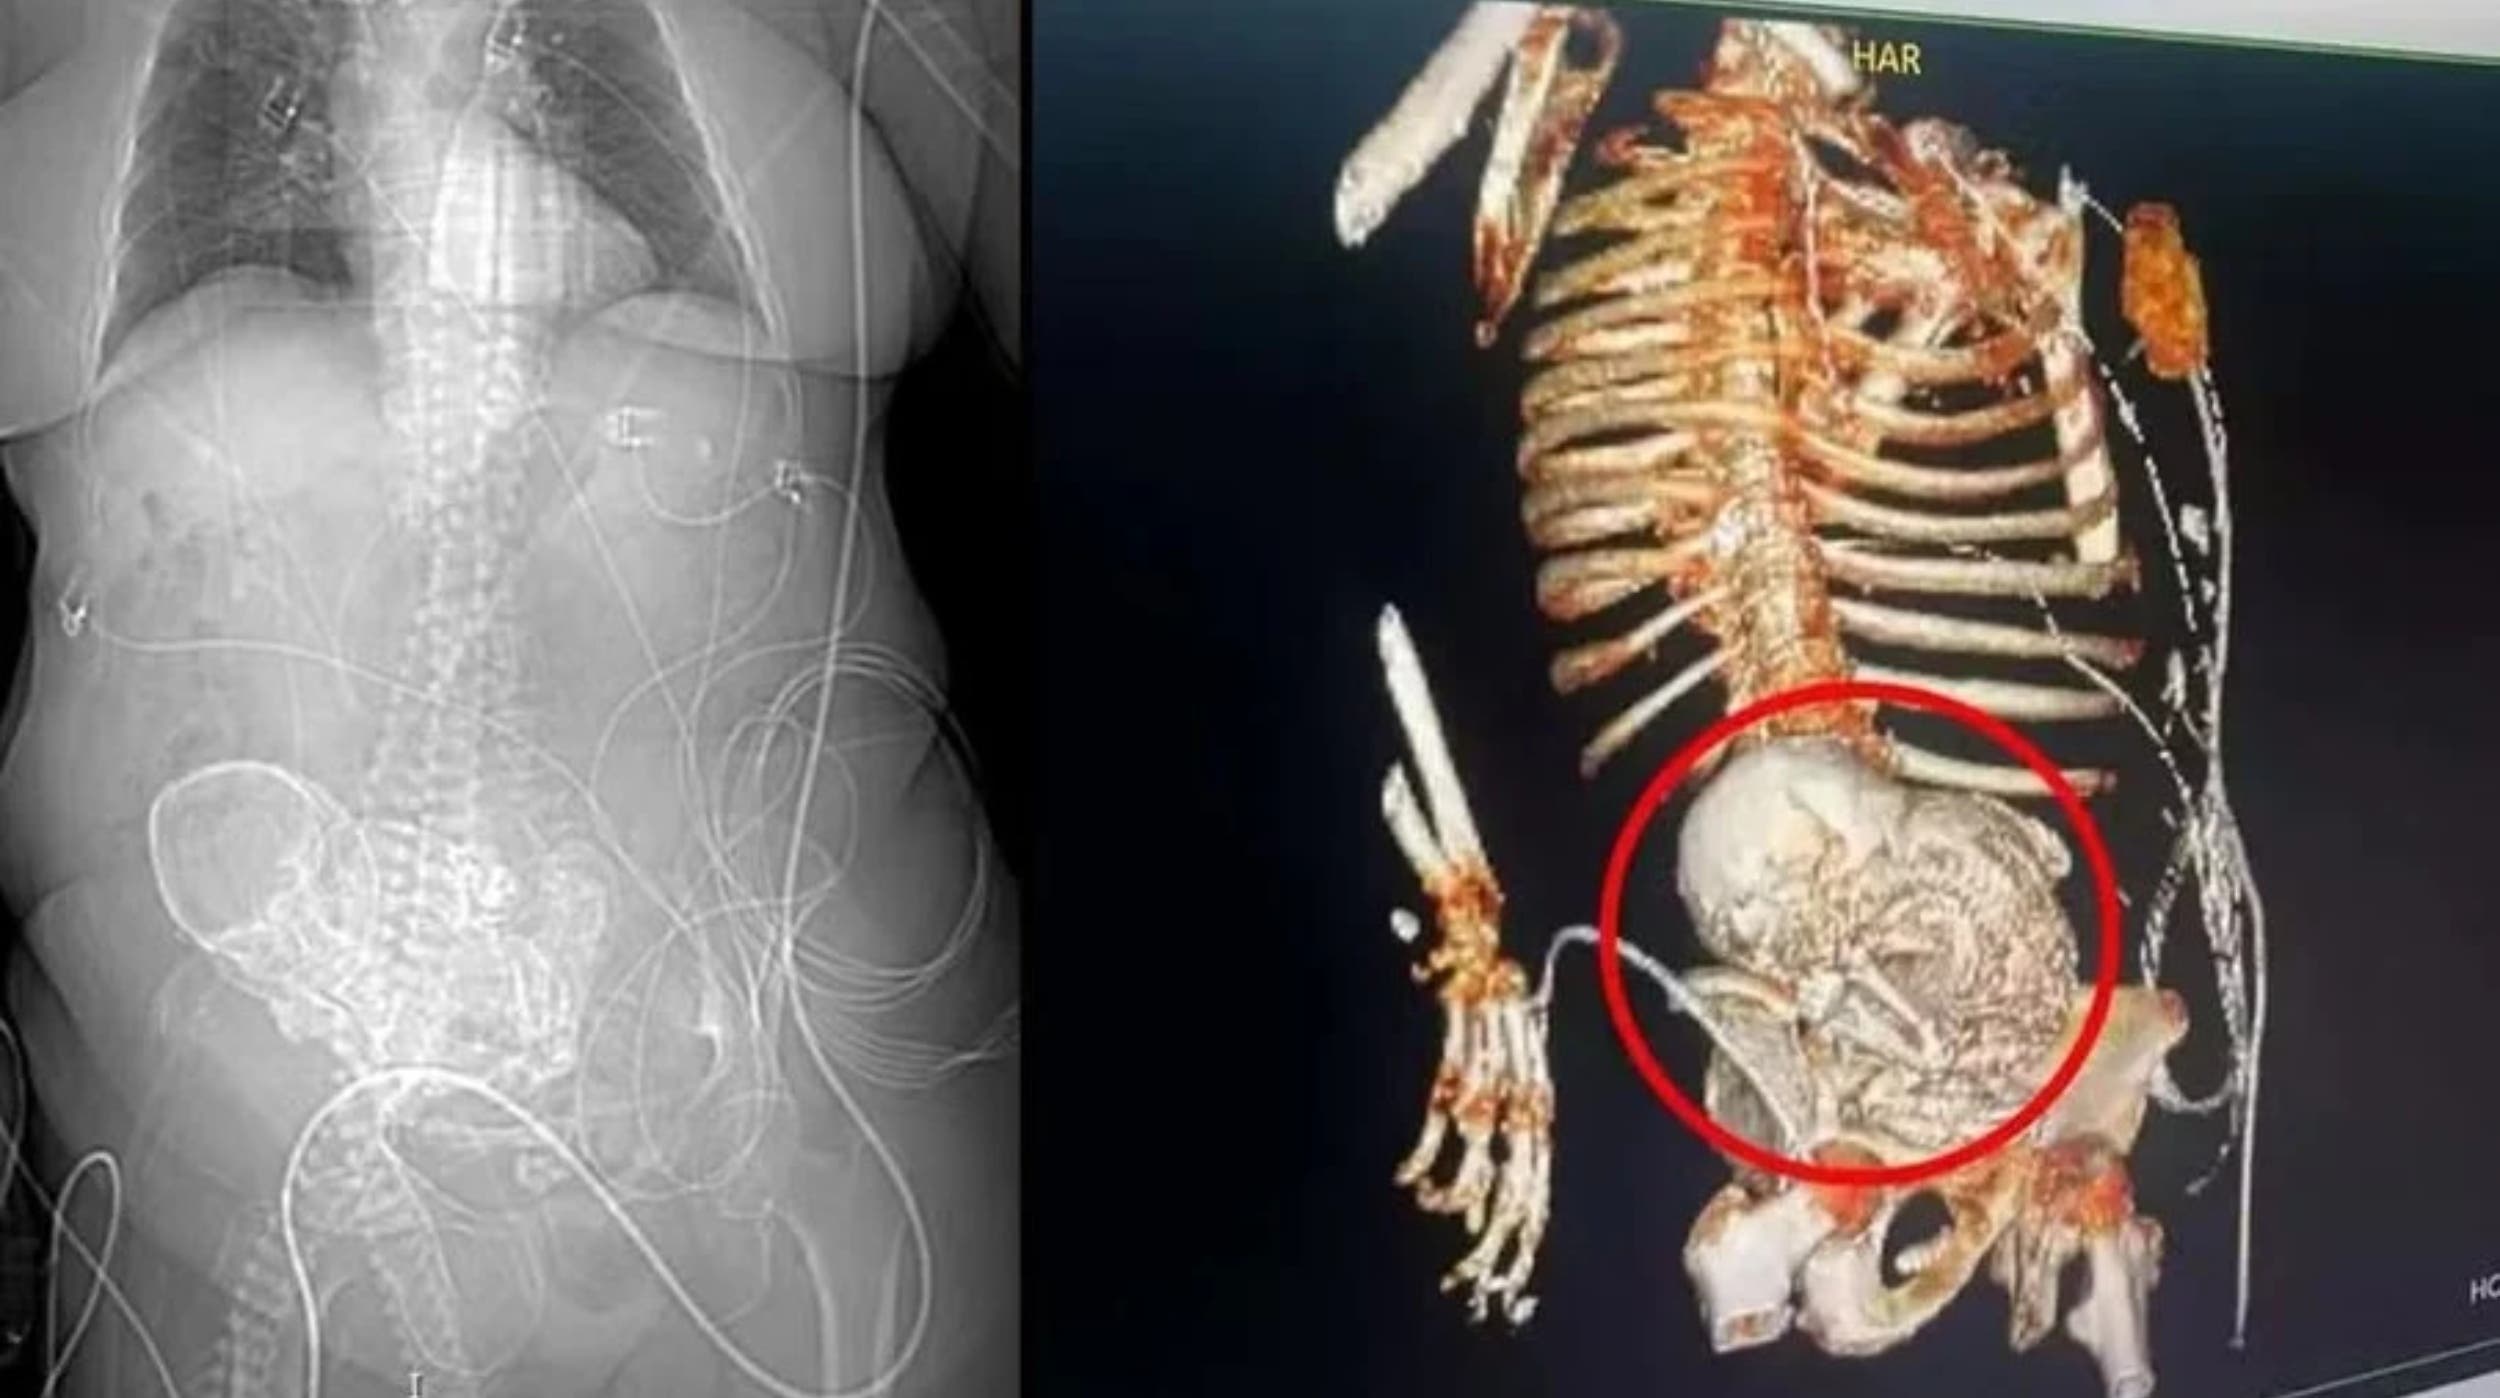

Los médicos descubrieron la presencia del "bebé de piedra" durante una tomografía realizada tras su llegada al hospital. La mujer, residente del municipio de Aral Moreira, había sufrido una caída la semana anterior, lo que inicialmente la llevó a consultar con un médico local. Debido a la gravedad de su estado, fue trasladada de urgencia al hospital de Ponta Porã.

La condición médica conocida como 'litopedia', es un fenómeno raro donde un óvulo fertilizado fuera del útero resulta en la muerte y posterior calcificación del feto. En el caso de esta mujer, se estima que el feto estuvo en su interior entre 30 y 40 años, desde su último embarazo.